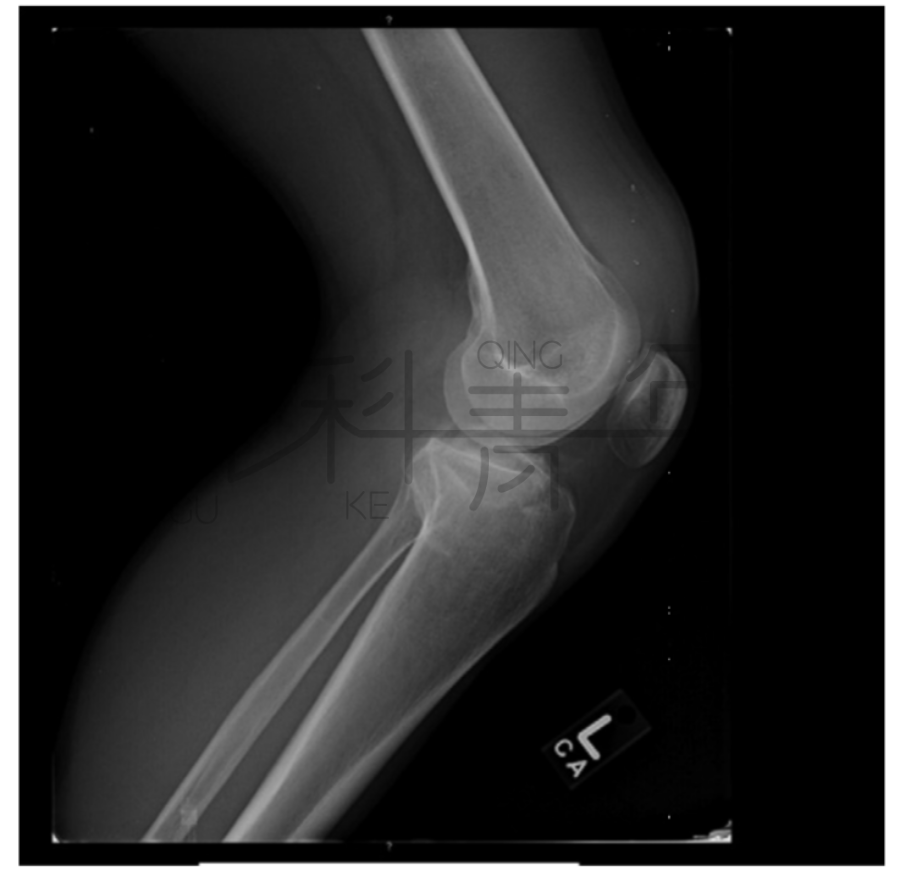

病例7 一例10岁患者肘关节外伤,侧位可见明显关节积脂血症。